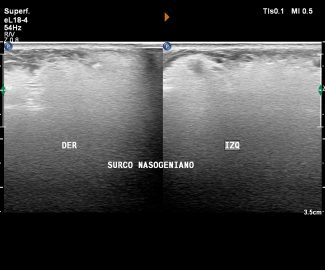

Especialista en diagnóstico por imágenes con más de 25 años de experiencia en el campo del ultrasonido y radiología digital. Trabajamos con equipos de alta tecnología garantizando la calidad y seguridad de nuestros diagnósticos, pues nuestra prioridad es la salud, bienestar y satisfacción de nuestros pacientes.

Sabemos que visitar un centro médico a veces genera nervios. Por eso, hemos creado un ambiente cálido, moderno y 100% seguro para ti. Desde nuestra cómoda sala de espera hasta nuestras áreas de ecografía, mamografía y rayos X, cada rincón está equipado con tecnología de última generación y diseñado para que te sientas en confianza.